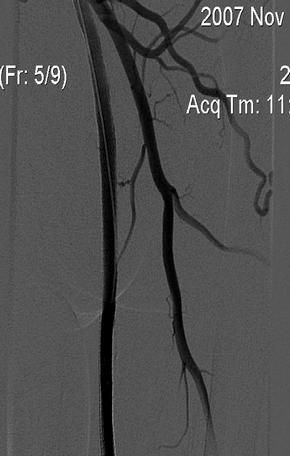

Установлены стенты Smart 6 x 150mm с постстентовой дилатацией баллоном OptaPro 6 x 60mm.